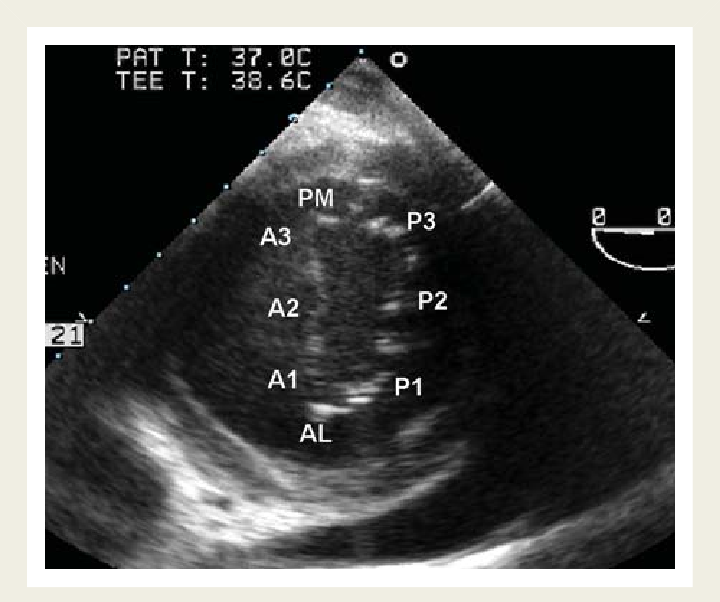

28

Mid Esophageal Mitral commissural view At 60 Degree